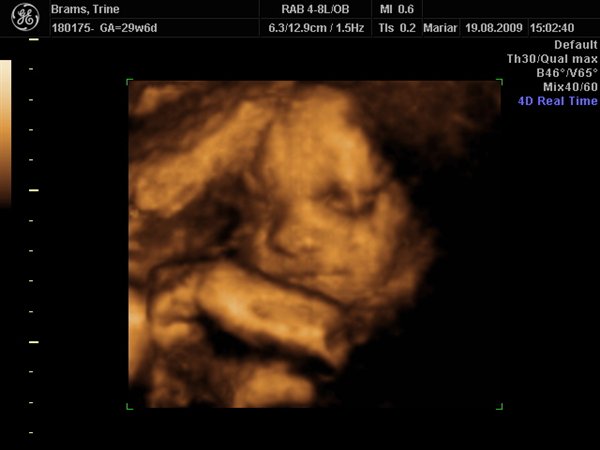

Jeg har lige været til en 3D/4D scanning (27+0), hvilket var en kæmpe oplevelse. Jeg venter en dreng på foreløbig 976 gram

Denne tråd er for alle os som har fået foretaget sådan en scanning. Jeg tænkte det kunne være sjovt at smide nogle fotos op af vores bebzere, da de lå i maven. I profil og forfra.

Skriv gerne hvilken uge scanningen er foretaget, samt evt. hvad køn det er